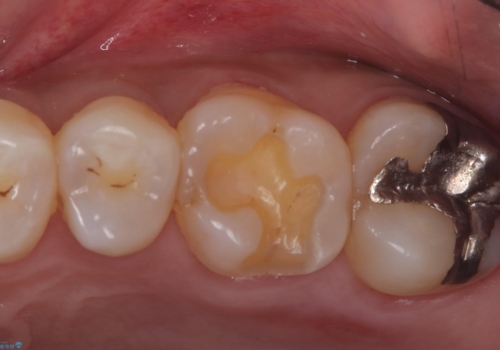

- 主訴:銀の詰め物が外れてしまった

保険適応のメタルインレーが脱離し、中が少し虫歯になっていたため審美性も良いセラミックインレーでのやり替えとなりました。

旧インレー窩洞内のカリエスと裏層を除去し、新たにCR裏層したうえでセラミックインレー修復を行いました。セラミックインレーセット時は、ラバーダム防湿を行っています。